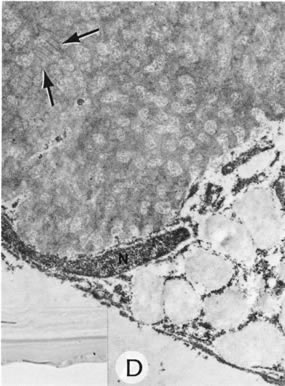

By light microscopy, eosinophilic intranuclear inclusions are characteristic of herpes simplex viral infections and represent the result of viral replication (Cowdri type A inclusions).121 Hypersensitivity type IV reactions in the stroma are characterized by lymphocytic and plasmacytic infiltrates. Intranuclear inclusions are relatively rare and are not found in most specimens. Viral particles occasionally can be found in multinucleated giant cells or within the stroma, especially in keratocytes (Figs. 20 and 21).

Fig. 20. Herpes simplex. A. Typical dendritic ulcer. B. Scanning electron micrograph of a dendritic ulcer in the epithelium of a rabbit cornea. C. Many intranuclear inclusions (arrows) are present in the corneal epithelium near the edge of the ulcer. D. Virus particles (arrows) of herpes simplex are present in the nucleus. E. Virus particles also are present within the cytoplasm. Note the large size of the cytoplasmic virions. Some particles show empty capsids, whereas others are complete, containing nucleoids. (Courtesy of SEI Photoarchives.) (B Courtesy of Dr. R. C. Eagle Jr; C from Font RL: Chronic ulcerative keratitis caused by herpes simplex virus. Arch Ophthalmol 90:382, 1973.)

Fig. 21. Herpes simplex. A. Clinical appearance of bullous keratopathy. B. Chronic condition shows development of bullous keratopathy. The anterior chamber inflammatory reaction contains multinucleated inflammatory giant cells (arrow), shown under high magnification in inset. C. Ulcerated bullous keratopathy (arrows). A corneal abscess (a) and hypopyon (h) are present. Note (inset) the subluxation of the lens to left, caused by the loss of zonula-lens attachments on the right, resulting in a “blunted” appearance of the right side of the lens. (Courtesy of SEI Photoarchives.)